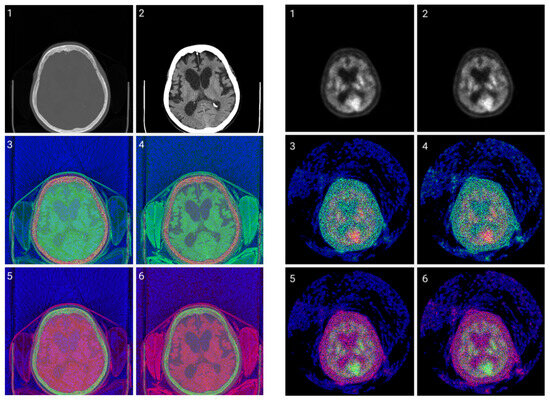

2.2. Method 1: Colormap Information Transform (CIT)

3.1. CIT Application

3.2. Colormap Folding Application